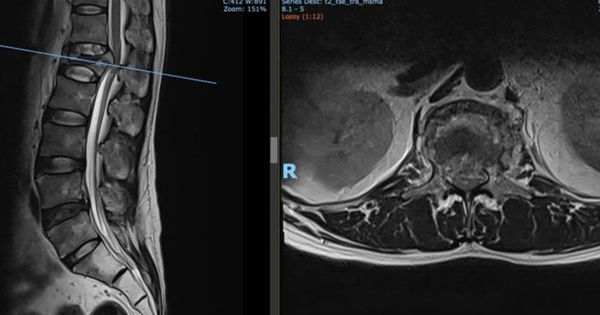

Sau tai nạn lao động, bệnh nhân đau lưng dữ dội, tê yếu hai chân, rối loạn tiểu tiện - dấu hiệu hội chứng chùm đuôi ngựa. Nhờ phẫu thuật kịp thời, vận động và sinh hoạt của bệnh nhân dần phục hồi, tránh nguy cơ liệt.